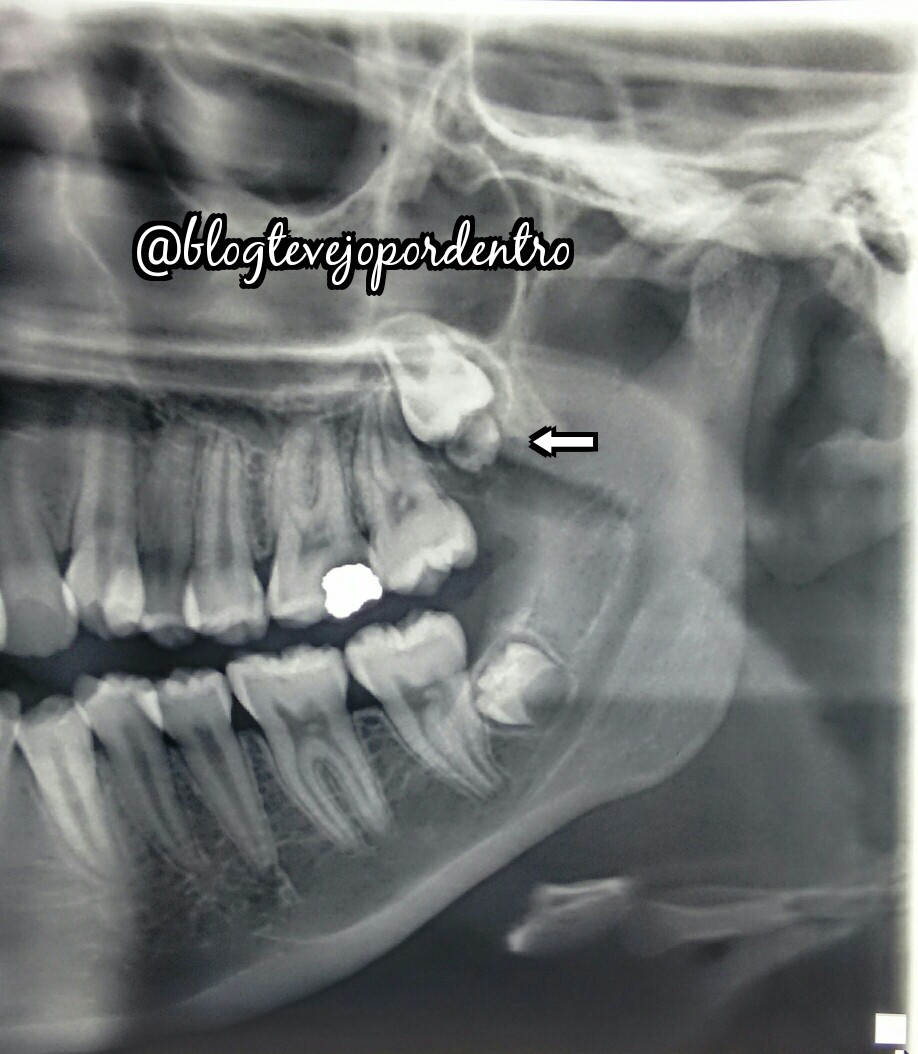

E temos um Dentinho...